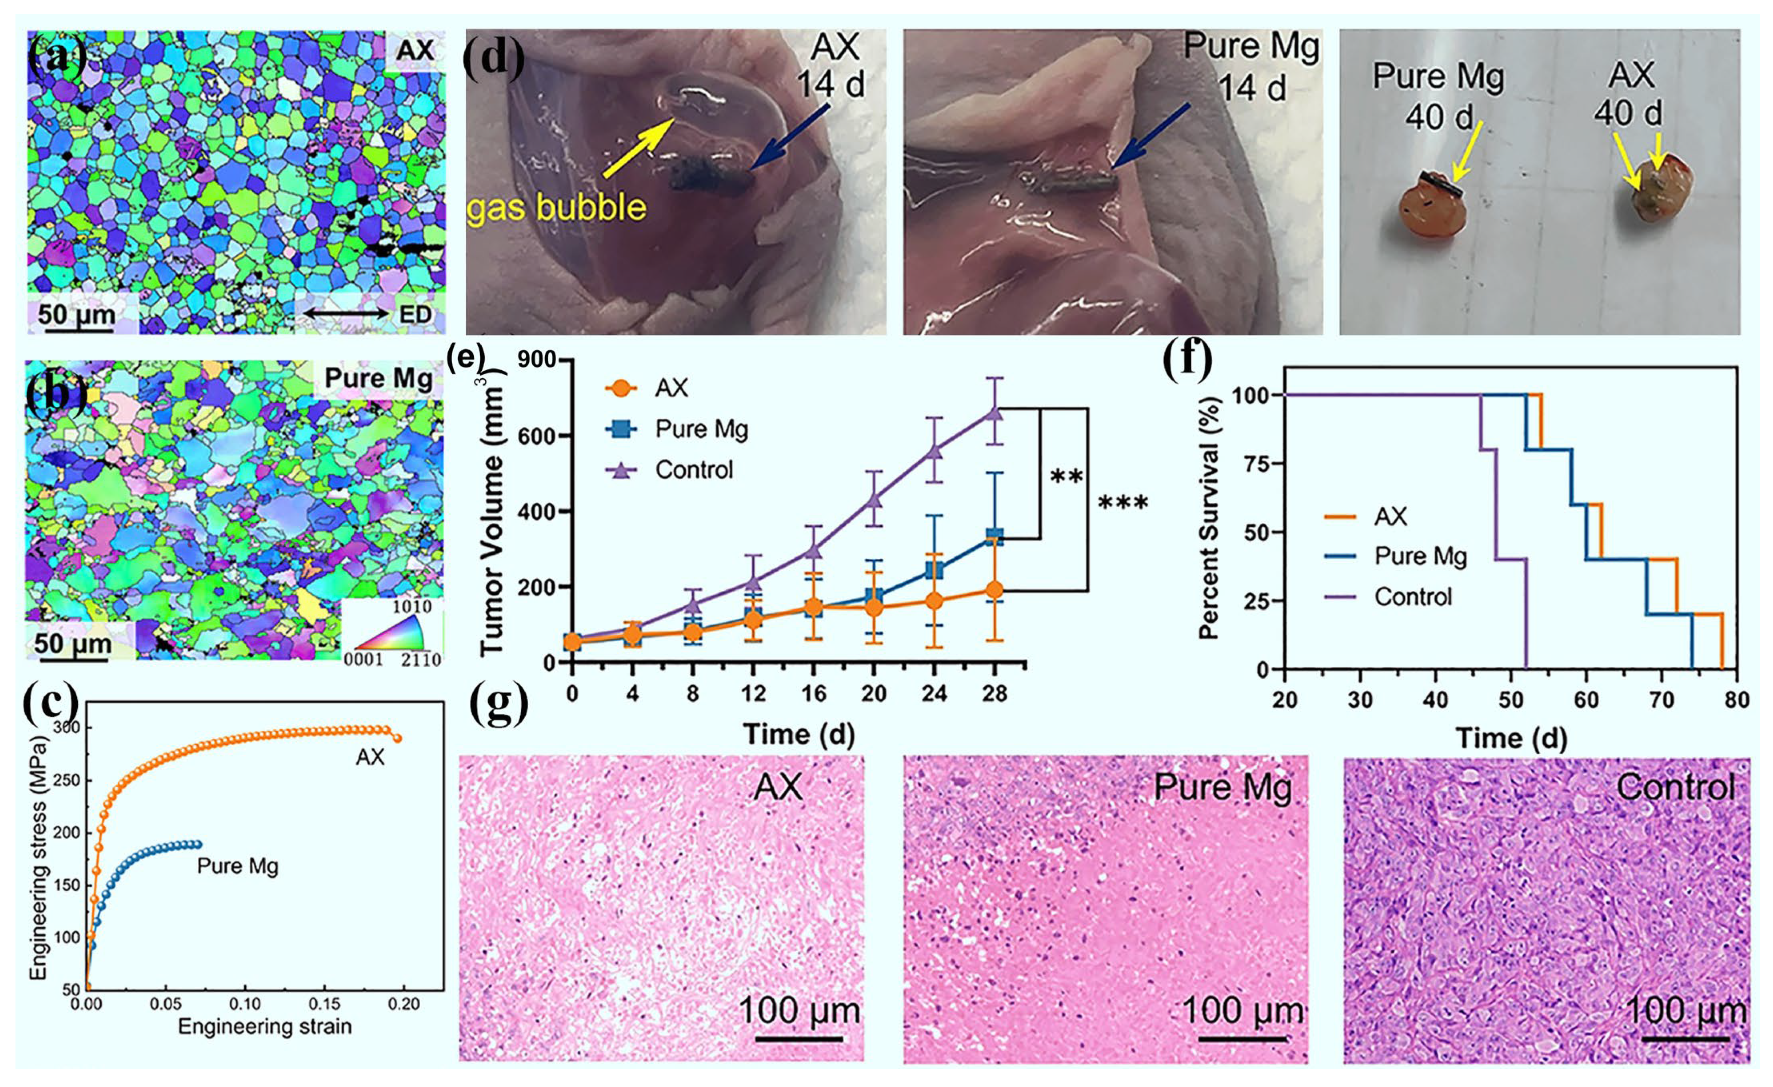

3.7. Tumor Treatment